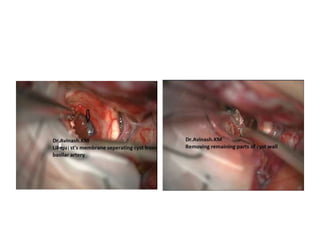

FIGURE 4. The capsule of the cystic craniopharyngioma was firmly attached to the left

hypothalamus, the stalk was dislocated to the right side (Patient 6). The outgrowth of the

craniopharyngioma from proximal stalk is recognizable A. Complete removal of the capsule was

possible, but produced subpial blood injection over the left hypothalamic surface B. MRI scan

revealed a small ischemic injury in the left hypothalamus C. This patient had transient sleep

disorder, moderate hyperphagia and memory problems (see also a supplemented video

material 1).

Craniopharyngioma removal -

Lilliquest membrane & Basillar artery